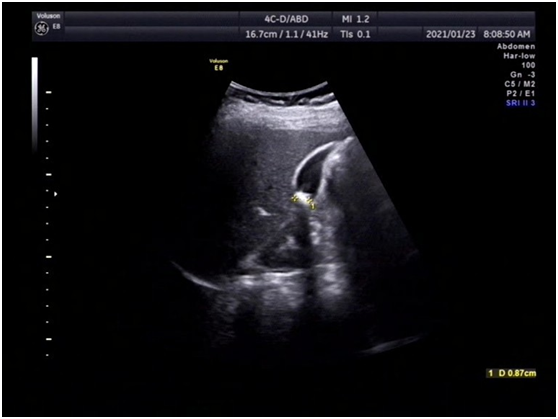

· 胆囊上长"肉肉",怎么办? ( ) 张先生, 34岁,近来一直感觉右上腹不适,经b超检查提示胆囊息肉样病变,已有1厘米大小,于是在医生的建议下做了胆囊切除术。术后,切除的胆囊病理检查报告提示慢性胆囊炎伴腺肌瘤样增生。 张先生的胆囊到底怎么了? 首先,我们说说胆囊息肉样0805 胆囊多发息肉怎么办呢? 0702 多发性胆囊息肉怎么办? 948; · 长了胆囊息肉怎么办? 近年来,人们在进行常规健康体检时,越来越多地被检查出胆囊"异常"——胆囊息肉。 胆囊上长出来的小息肉虽对日常生活不会有太大影响,但却让不少患者心理蒙上了一层"癌变"的阴影。 在临床上,针对"胆囊息肉"的治疗分为两种,一种只需观察治疗,定期复查即可,另一种则建议尽早手术切除,以防癌变。 那么,长了胆囊息肉

胆囊息肉怎么办- · 胆囊息肉、胆囊结石严重吗? 胆囊息肉指胆囊内生长出来的息肉样的病变,其中大多数小于10cm的胆囊息肉是良性的疾病,恶变的几率较低,不必过分忧虑,只需要定期复查即可。 但是大于10cm以上的则有癌变的可能,此时就需要提高警惕必要时手术治疗,以避免贻误病情。 胆囊结石是胆道系统最常见的一类疾病,结石本身对身体没有影响,但其可能引起胆囊炎 · 胆囊上长"肉肉",怎么办? 21 04/17 分享 评论 复旦大学附属华山医院 aa 张先生,34岁,近来一直感觉右上腹不适,经b超检查提示胆囊息肉样病变,已有1厘米大小,于是在医生的建议下做了胆囊切除术。术后,切除的胆囊病理检查报告提示慢性胆囊炎伴腺肌瘤样增生。 张先生的胆囊到底怎么